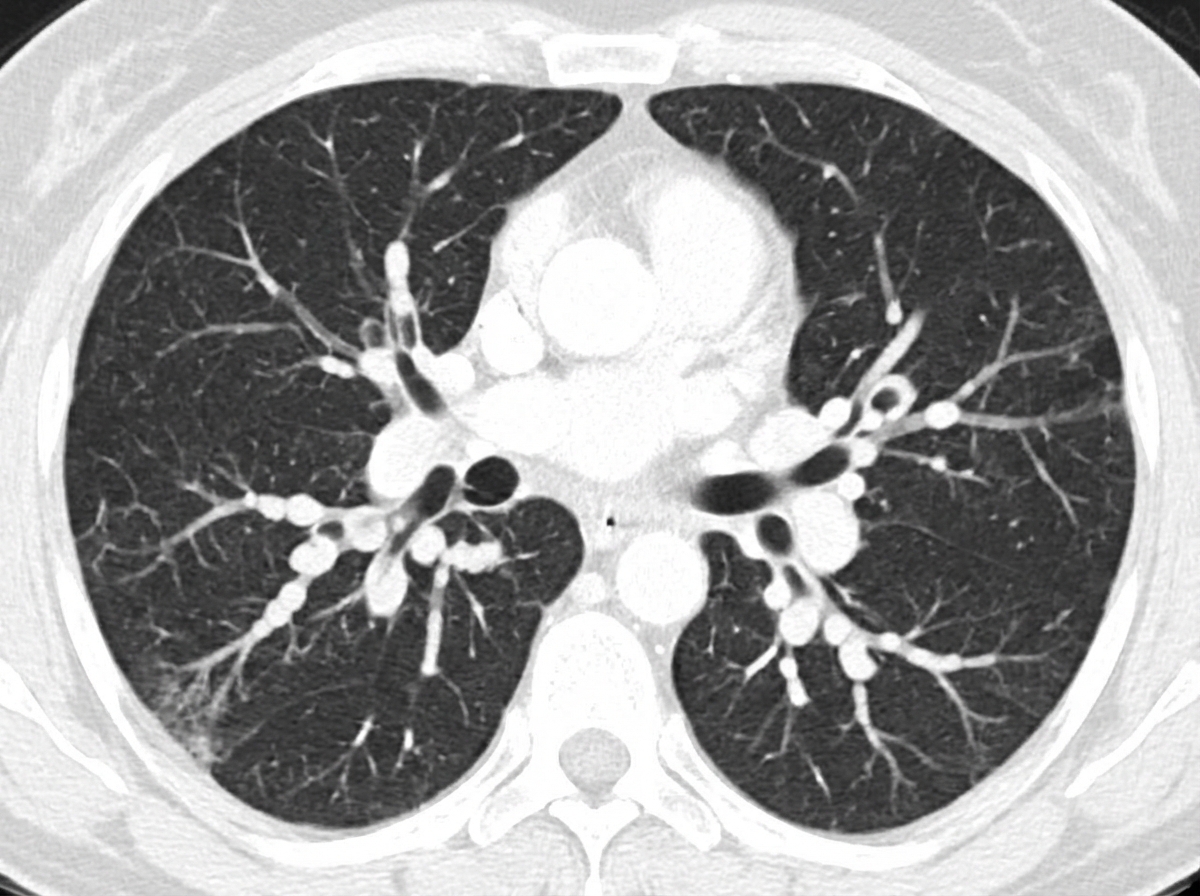

A patient presents with chronic productive cough and clubbing, with coarse rales on auscultation. What is the diagnosis suggested by the CT scan shown?

Explanation: ***Bilateral varicose bronchiectasis*** - The clinical triad of **chronic productive cough**, **digital clubbing**, and **coarse rales** is pathognomonic for bronchiectasis, with varicose type showing characteristic **beaded/irregular dilations** on CT. - CT demonstrates the **signet-ring sign** (dilated bronchi larger than adjacent vessels) and **bronchial wall thickening**, confirming irreversible airway dilatation. *Multiple cavitating secondaries* - Would present with **multiple thick-walled cavities** scattered throughout both lungs, typically in **peripheral locations**. - Associated with **weight loss**, **hemoptysis**, and a **known primary malignancy** (commonly lung, kidney, or head & neck cancers). *Interstitial fibrosis* - Characterized by **fine inspiratory crackles** rather than coarse rales, with **honeycombing** and **reticular patterns** on CT. - Typically causes **restrictive lung disease** with reduced lung volumes, not the obstructive pattern seen in bronchiectasis. *Miliary tuberculosis* - Shows **diffuse small nodules** (1-3mm) with uniform distribution throughout both lung fields on CT. - Presents with **systemic symptoms** like fever, night sweats, and weight loss, often in **immunocompromised patients**.